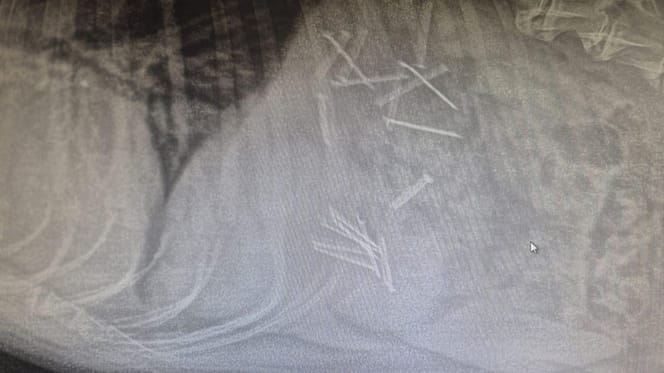

Zdjęcie RTG żołądka psa

Dzięki błyskawicznej reakcji opiekunki i natychmiastowej interwencji lekarzy z lokalnej kliniki weterynaryjnej, życie czworonoga udało się uratować. Z jego przewodu pokarmowego usunięto aż 18 gwoździ!

Lekarze byli w szoku, kiedy zobaczyli prześwietlenie RTG.